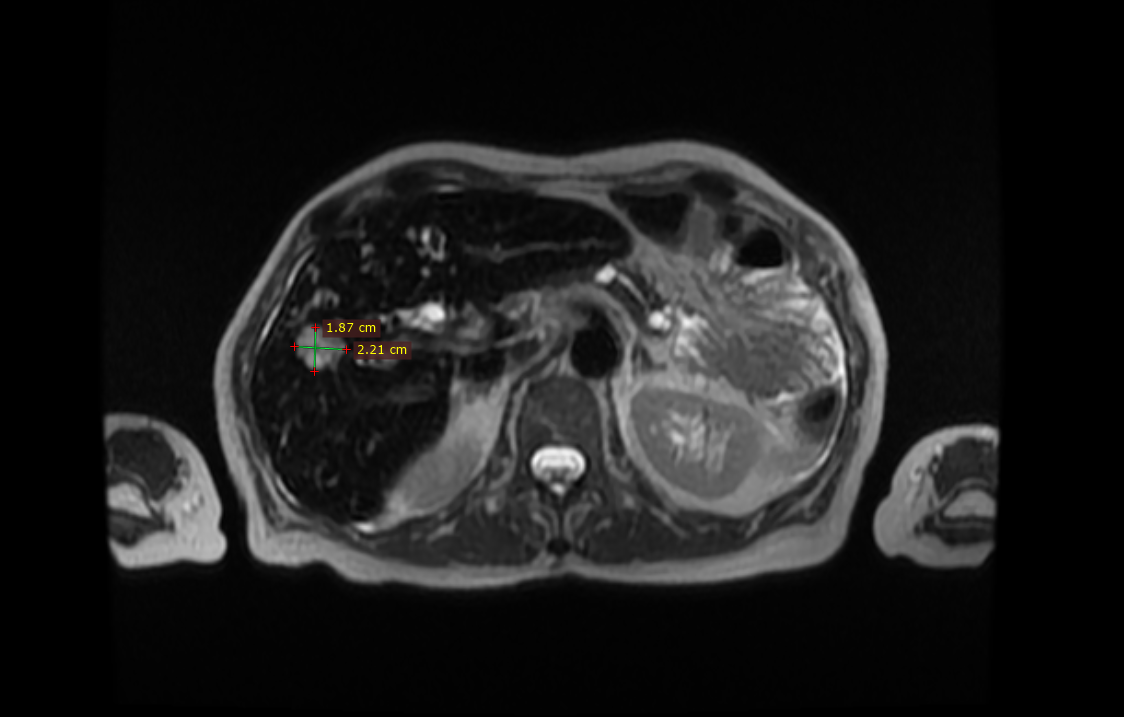

Принято решение о возврате к химиотерапии второй линии. Было проведено 6 курсов nab-паклитаксел+гемцитабин с разнонаправленной динамикой: практически все очаги в печени исчезли, но один очаг, расположенный в правой доле печени, увеличился в размерах почти в два раза.

Метастаз рака поджелудочной железы в правой доле печени